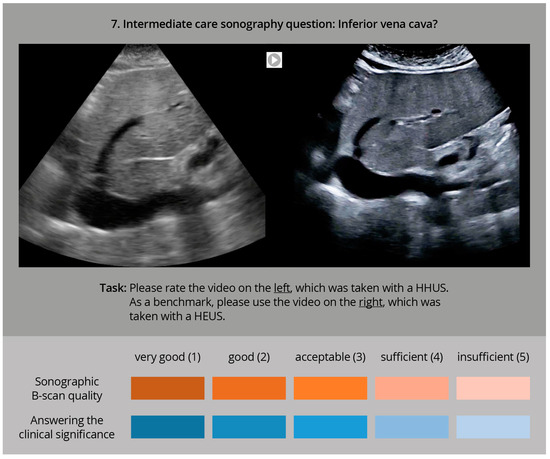

2.5. The Sonographic Questions

| 1. | Inferior Vena Cava (IVC) | Diameter and variability of IVC, volume status | Median sagital section | Far field | up to 12 cm |